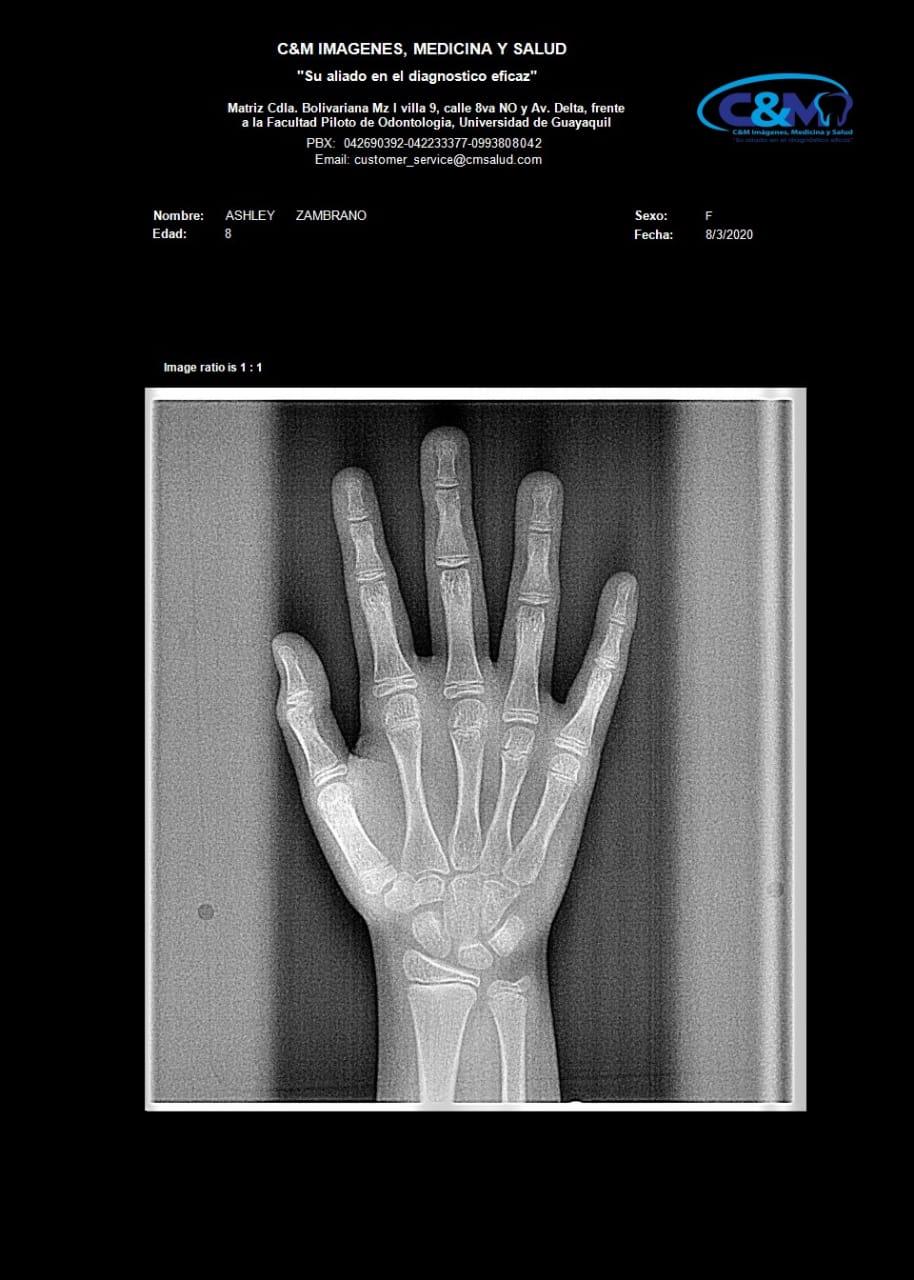

CARPAL